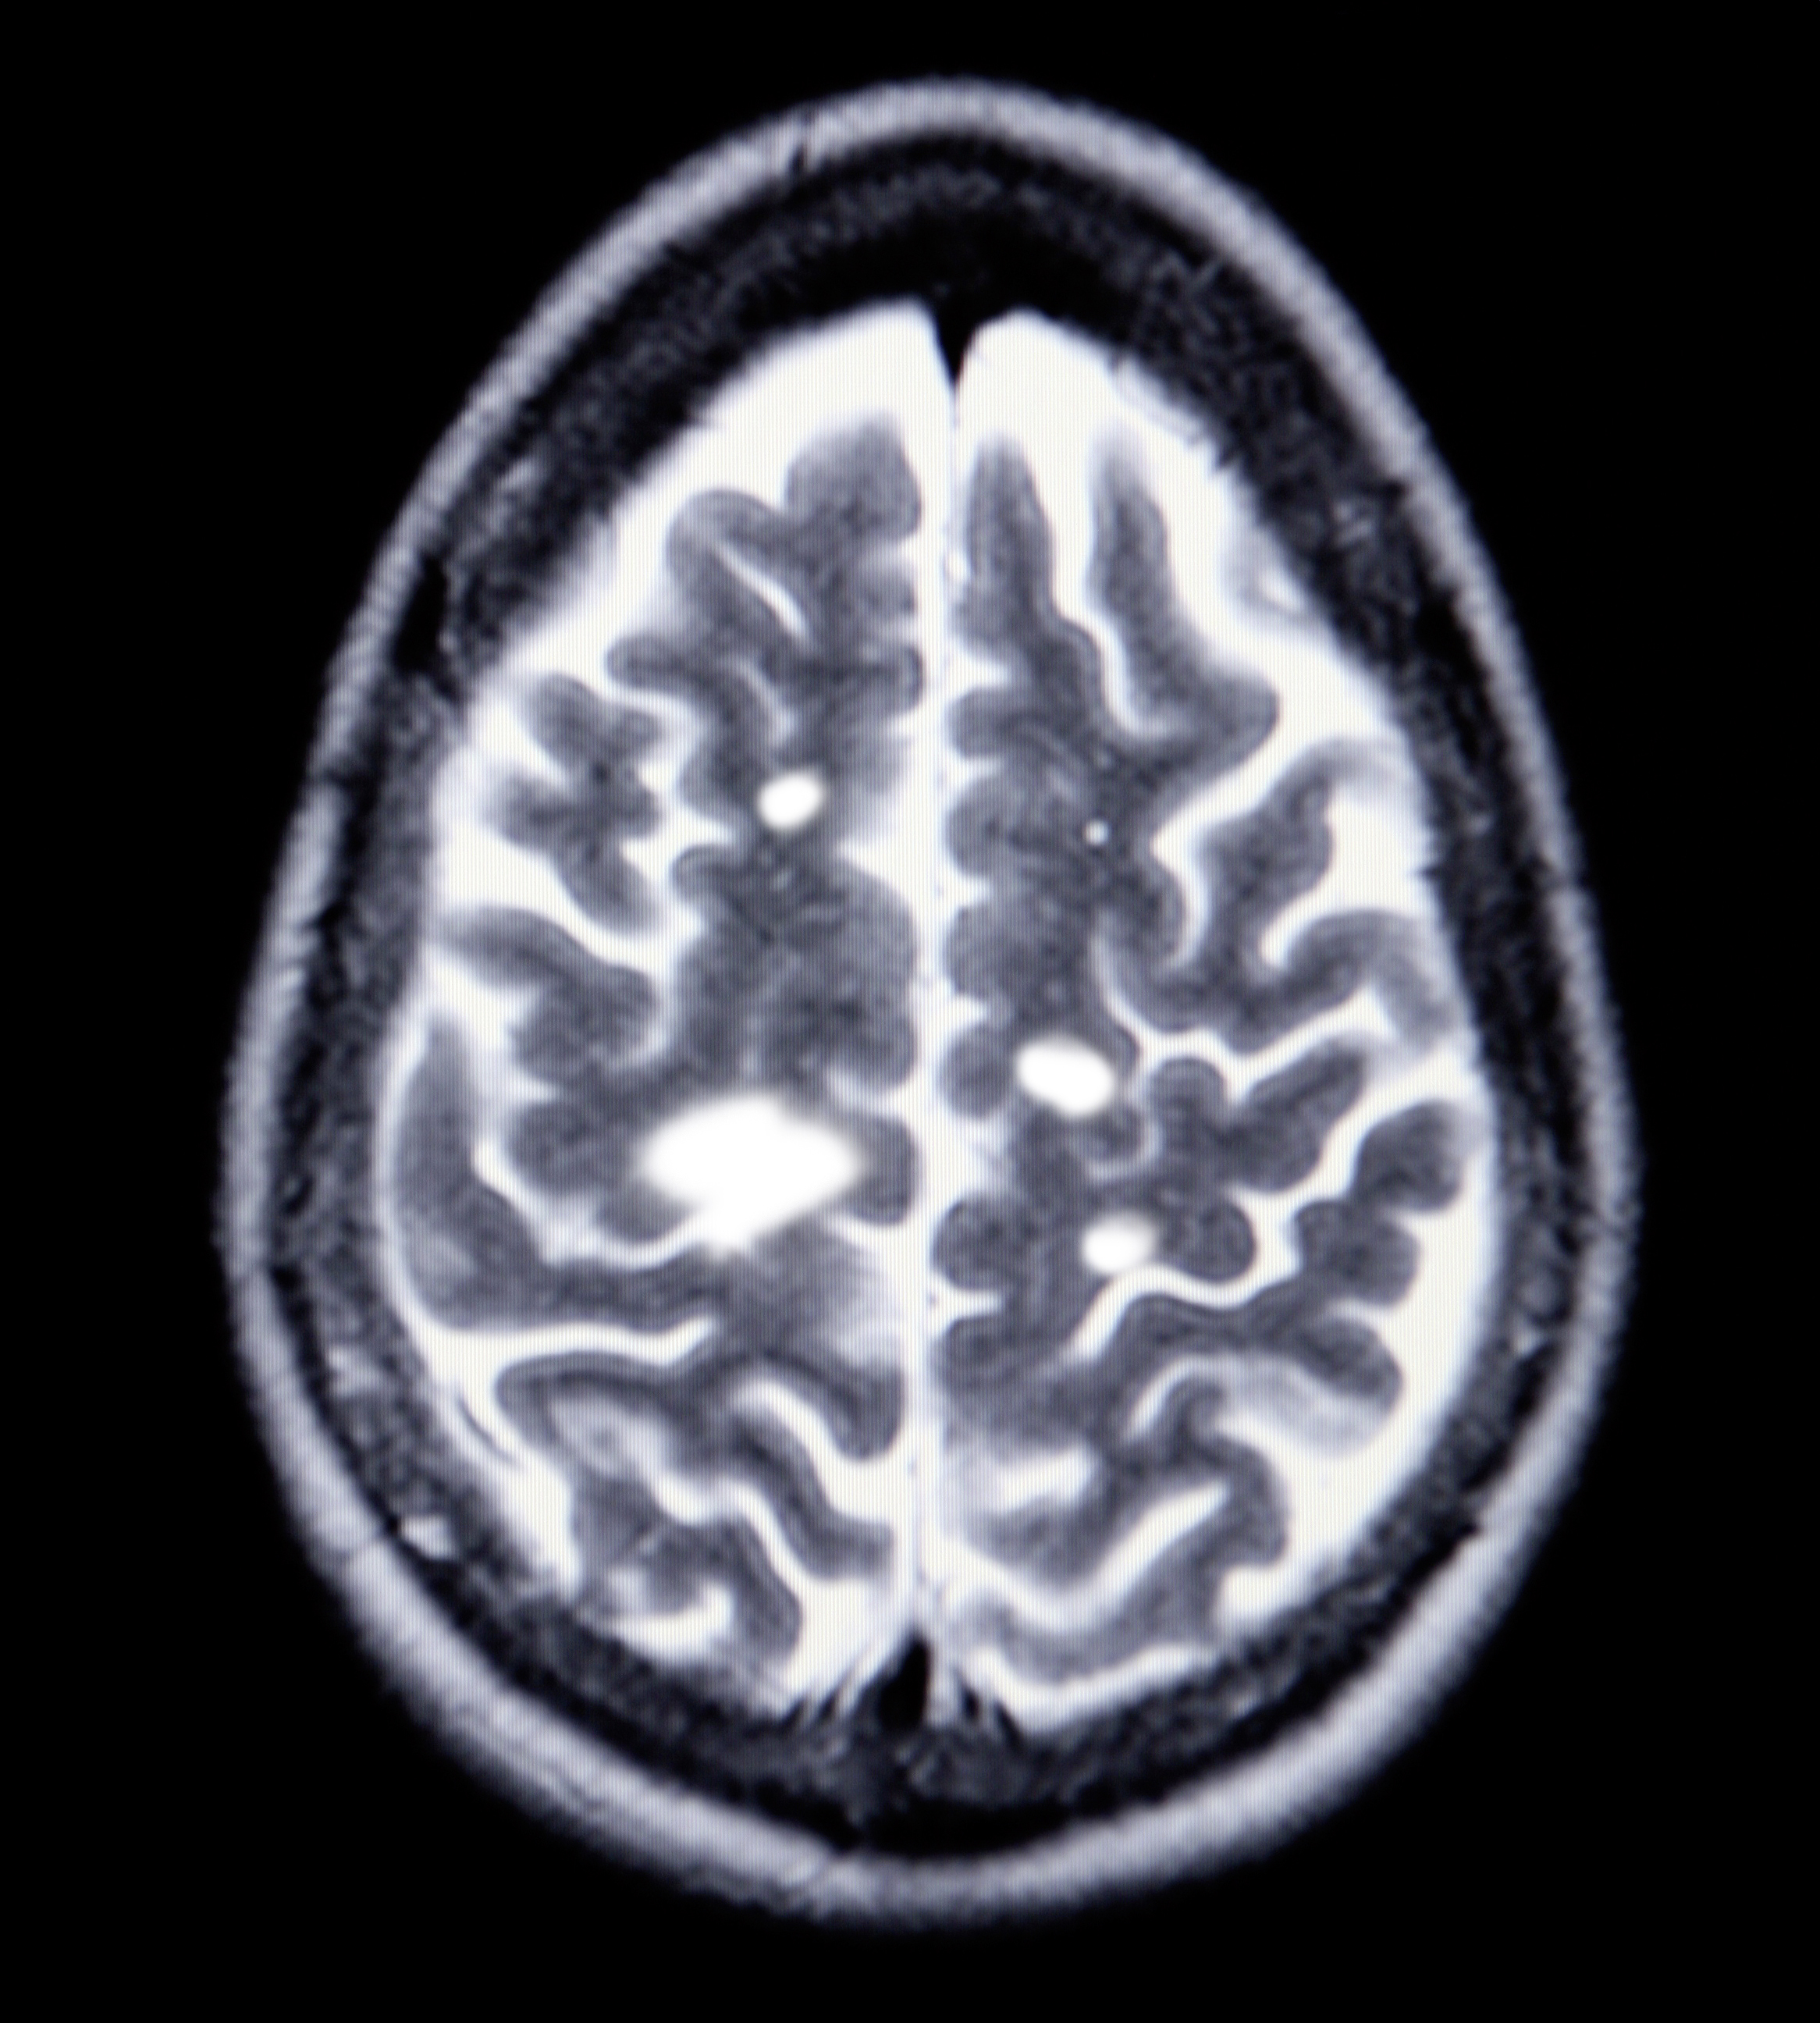

De eerste aanwijzing krijgt de arts gewoonlijk tijdens het lichamelijk onderzoek dat hij uitvoert naar aanleiding van klachten over de typische symptomen (zie hoofdstuk “symptomen”). Bij een vermoeden van MS kan een MRI-scan uitsluitsel bieden.

Aan de hand van een inspuiting met contrastvloeistof toont deze techniek de al dan niet beschadigde myeline in de hersenen.

De witte vlekken op de MRI-scan van de hersenen zijn de littekens, die ontstaan op plaatsen waar myeline werd afgebroken.